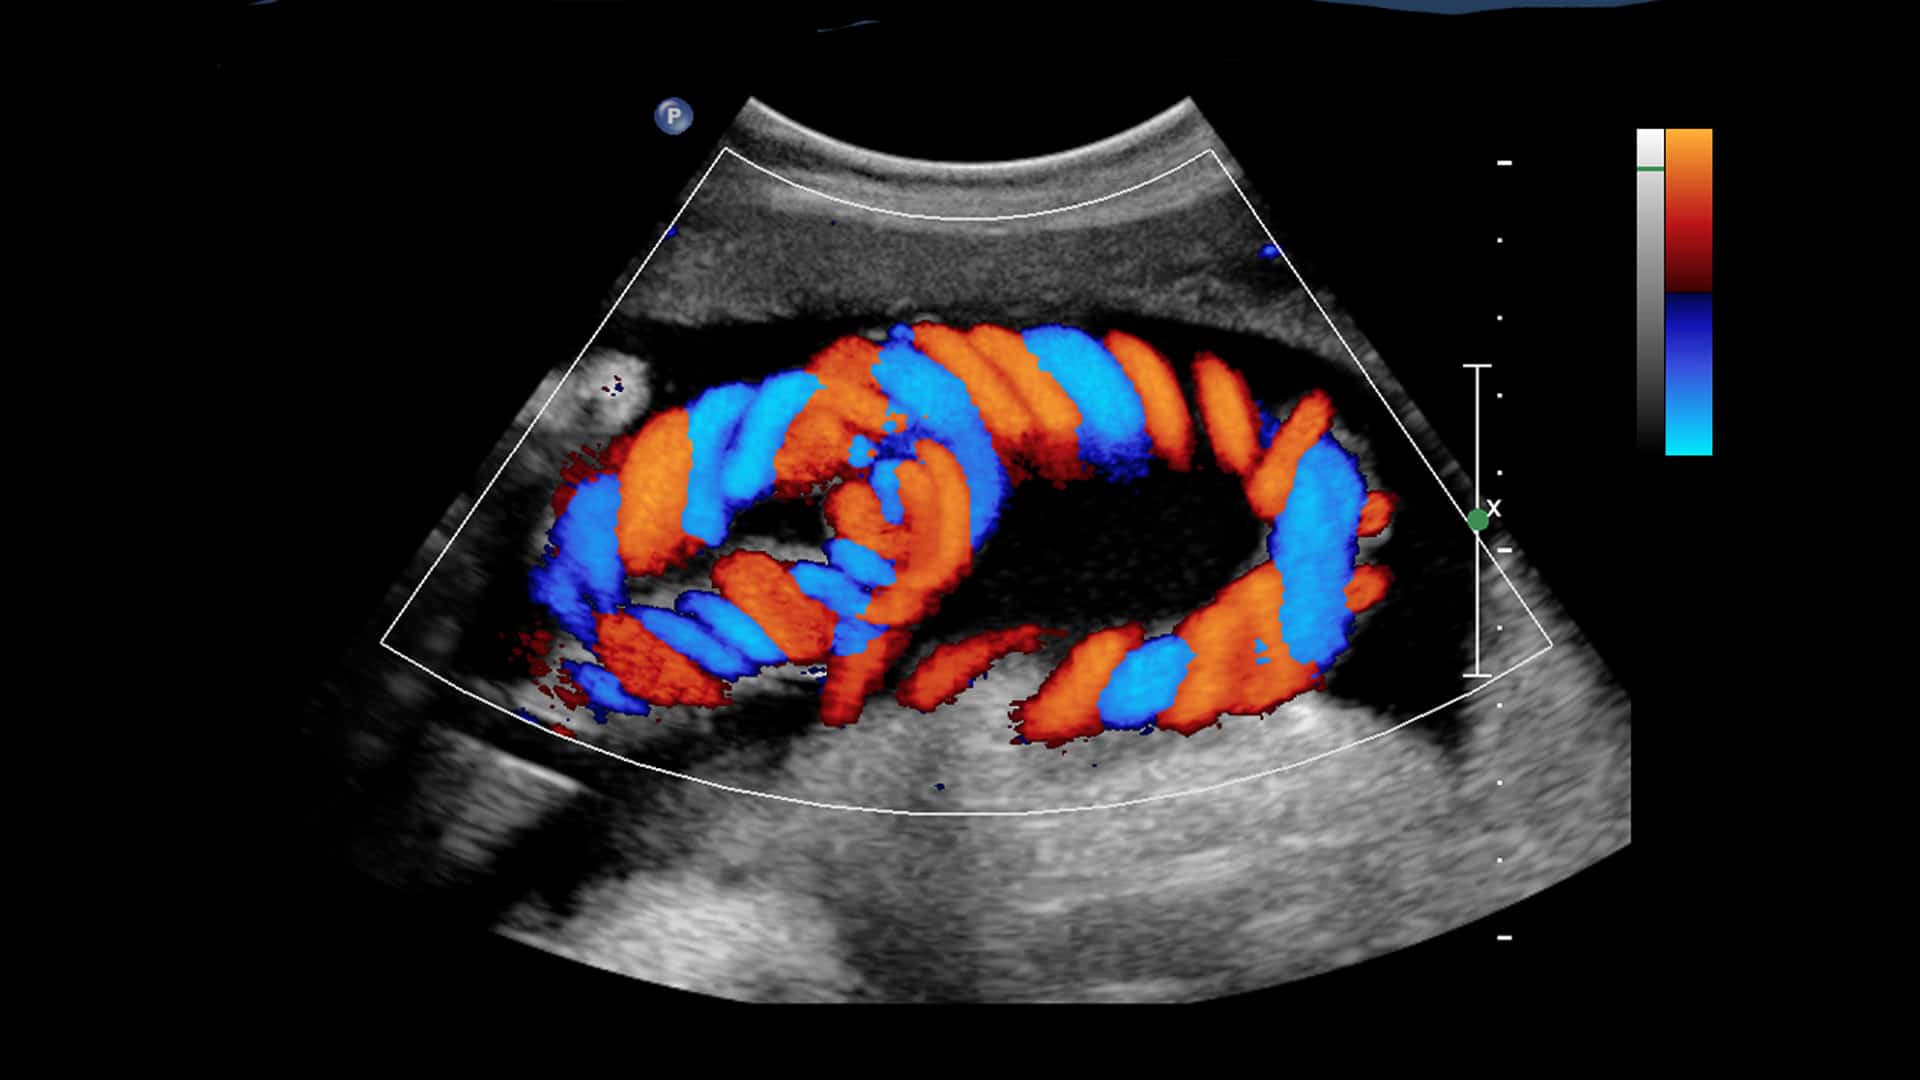

Color Doppler Services at NDRC

At NDRC, we provide advanced Color Doppler imaging services to evaluate blood flow through vessels and organs in real time. This non-invasive technique helps detect blockages, clots, and vascular abnormalities with high accuracy and safety.